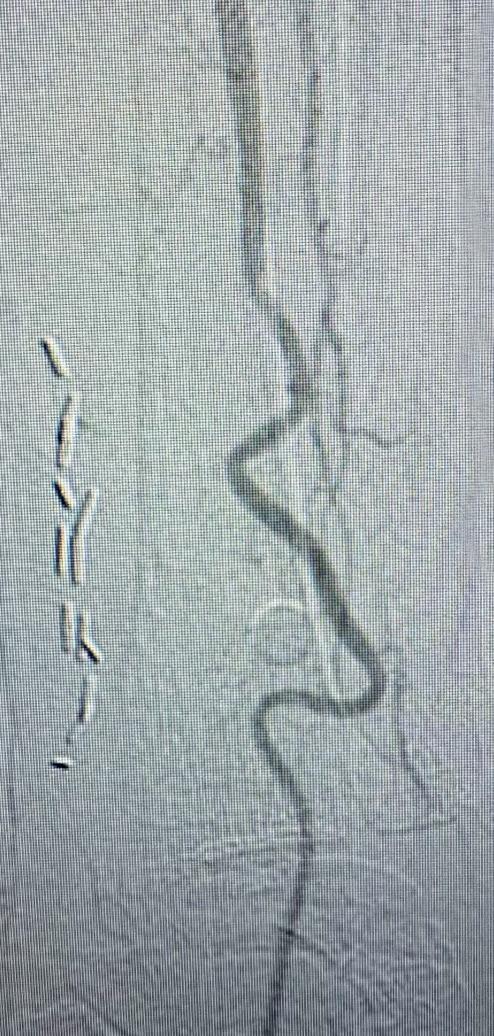

Shockwave E8 3mm x 80mm to the posterior tibial artery

The posterior tibial artery was successfully crossed first. The long-length posterior tibial artery disease was treated with a Shockwave E8 3.0mm x 80mm IVL catheter, with no pre-dilatation required. A total of 200 pulses were delivered along the length of the posterior tibial artery (Figure 3).

Shockwave E8 3mm x 80mm to the peroneal artery

Following this, the peroneal artery occlusion was successfully crossed. The longlength peroneal artery disease was treated with the same Shockwave E8 3mm x 80mm IVL catheter also with no pre-dilatation required. The remaining 200 pulses were

delivered across the length of the peroneal artery disease (Figure 3).

Left SFA intervention

To ensure adequate inline blood flow to the tibial vessels, the SFA disease was treated with drug-coated balloon angioplasty, followed by self-expanding stent placement.

Post-intervention arteriogram

An excellent technical result was achieved. The SFA was widely patent with no significant residual stenosis. The posterior tibial and peroneal arteries were widely patent with brisk flow and no residual stenosis. Significantly improved flow was identified to the foot (Figure 4).